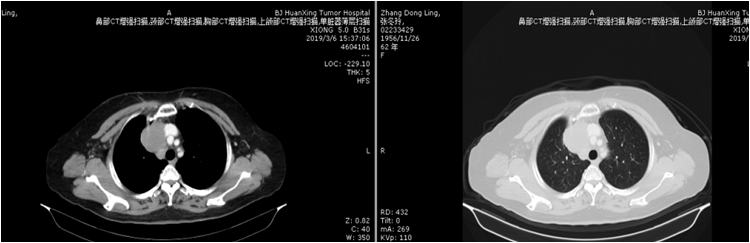

1、右前上纵隔肿物,最大截面约5.5X4.9cm,病变侵犯右侧头臂静脉、上腔 静脉、头臂静脉弓。

2、右下颈深、右侧颈后区、右侧锁骨上区、右侧气管食管沟、纵隔(2R、4R区)及右肺门可见多发肿大淋巴结,大者短径约1.5cm。